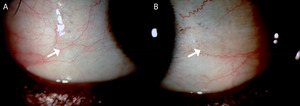

At presentation, the patient appeared lethargic and cachectic. Uncorrected visual acuities were 20/20 in each eye. Undilated examination revealed moderate punctate epithelial erosions in both eyes and 2-mm elevated gray lesions with a foamy surface on the temporal and nasal conjunctiva of the right eye and the temporal conjunctiva of the left eye, consistent with Bitot spots (Figure 1). Upon further questioning, the patient endorsed having poor vision at night in both eyes. The patient was prescribed fluorometholone 0.1% 4 times a day in both eyes, artificial tears 4 times a day in both eyes, and white petrolatum/mineral oil ophthalmic ointment at night in both eyes. The patient’s primary care provider was consulted, and an assay of vitamin A was ordered. Because of time constraints, a dilated eye examination was scheduled for 2 weeks later.

_temporal_and_(b)_nasal_conjunctiva_of_the_right_eye_at_present.jpeg)